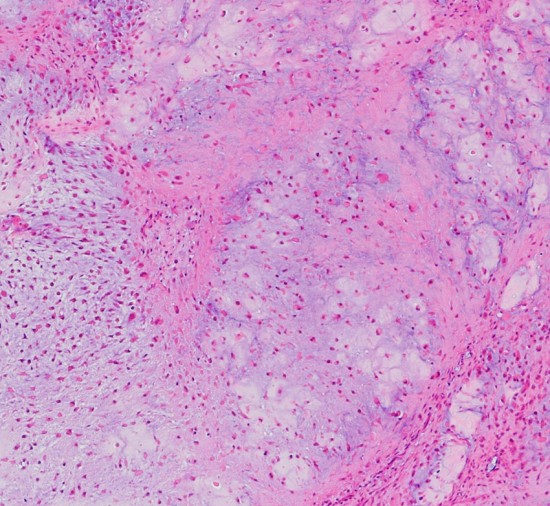

病理

低悪性度軟骨肉腫の病理像 grade 2 chondrosarcoma

背景は好塩基性の軟骨基質(粘液状 myxoid,軟骨様 chondroid)です。好酸性胞体をもつ異型紡錘形ないし上皮様細胞が多結節状に増殖しています。細胞密度はやや高い部分もあり,核は濃縮され大小不同や2核の細胞も見られます。MIB-1 index 3%